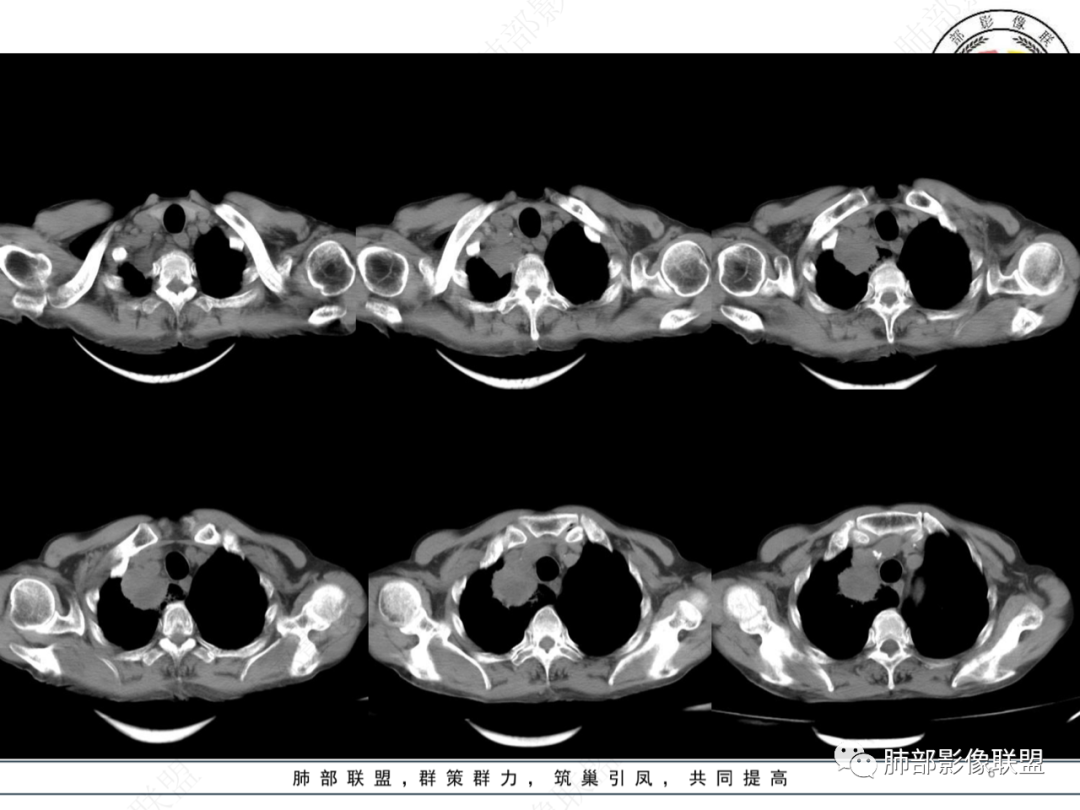

最让人忐忑的:淋巴结

炎性:结核多见,肿瘤:鳞癌多见

最让人放心不下的是这里

上腔静脉外面按理没有淋巴结啊

考虑肿瘤?右肺上叶高密度影,边缘模糊,侵及纵隔及胸廓入口,病灶密度不均匀,部分支气管截断,增强后不均匀强化,内可见较大范围坏死,纵隔多发肿大淋巴结不均匀强化。肺上沟瘤不能排除。